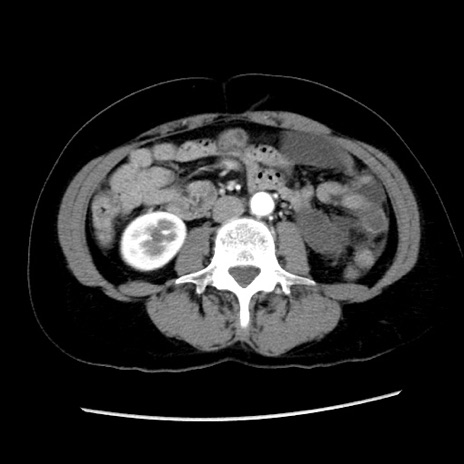

症例10(横断像)

【症例】 50歳代女性

【主訴】 腹痛

【現病歴】前日生レバーを食べた。今朝に排便あり。 昼前に突然発症の腹痛を生じ、当院救急外来を受診した。

【身体所見】 意識清明、腹部:平坦、軟、下腹部やや左を中心に圧痛・反跳痛あり、筋性防御あり

【データ】WBC 7800、CRP 0.07